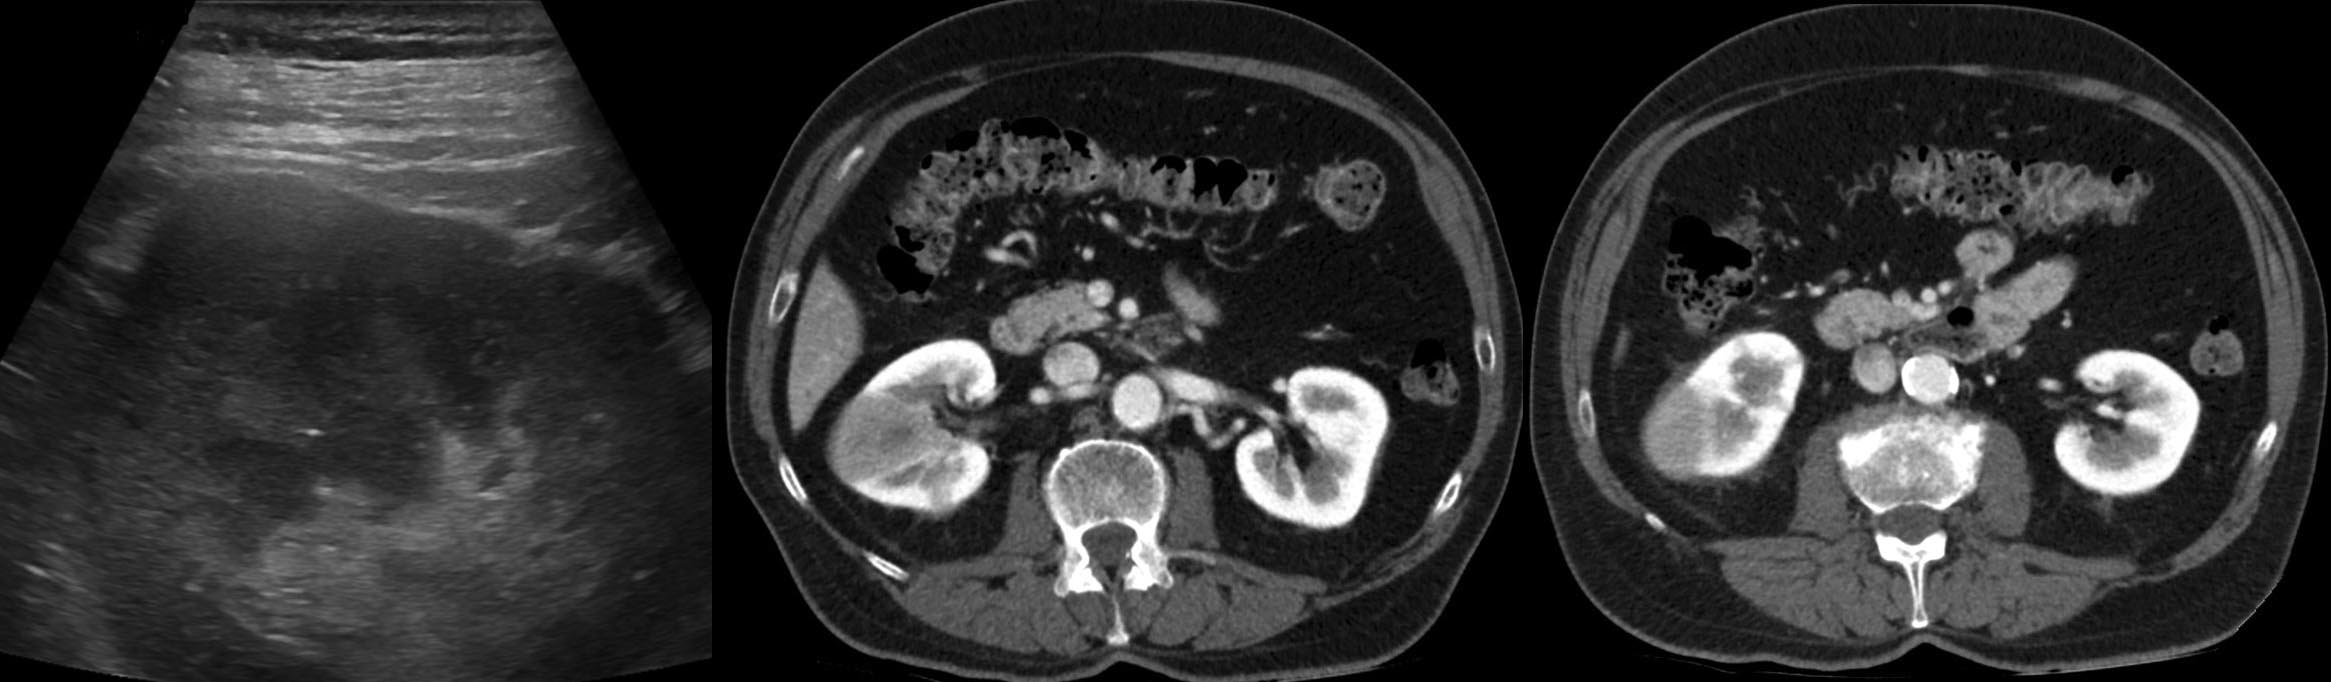

Eco y TC abdominal de control.